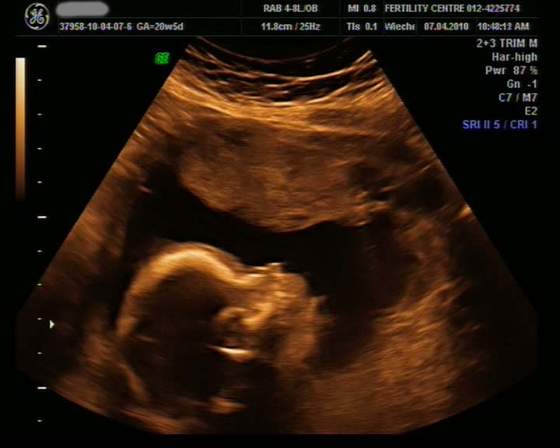

dziewczyny oto dowód na to że moja dzidzia to chłopczykśliczna stojąca fujarka:-)

No dokładnie,takie wypustki to na zdjeciach mój synek (w poprzedniej ciązy) miał na głowie ,raczkach i dłoniach,bo w tych miejscach był przytulony do powłok macicy i tak to zmieniało obraz.A tak jeszcze odnośnie tych zdjęć USG to niektore strasznie "zmieniają rzeczywistość" i tam gdzie nam się wydaje że jest główka to jest pupka ... to tak tylko dla przykładu